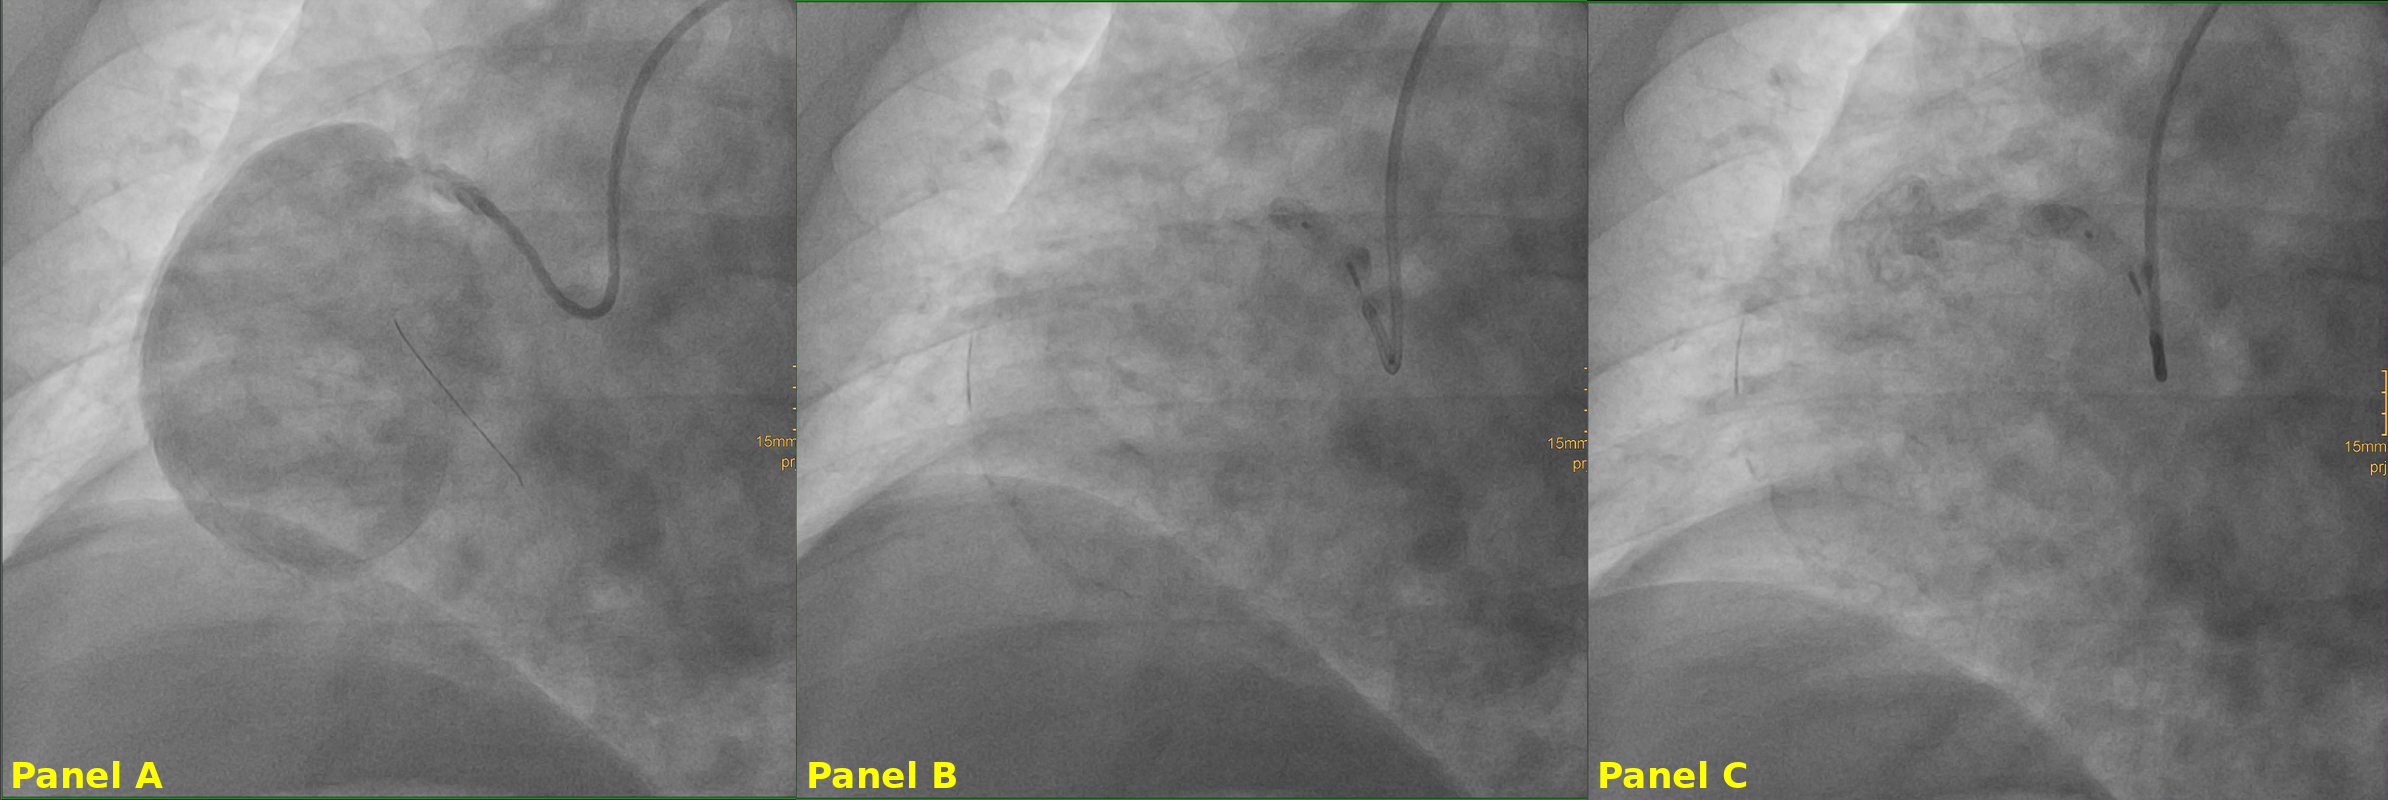

The patient remained hemodynamically stable and was initially discharged on optimal medical therapy. Coronary angiography revealed RCA occlusion with retrograde perfusion via left anterior descending artery collaterals. After multidisciplinary Heart Team discussion, conservative management was initially considered. However, due to aneurysm size and risk of complications, an endovascular approach was pursued.

The patient underwent percutaneous intervention under conscious sedation, utilizing dual arterial access (right femoral and left radial). The procedure included selective RCA catheterization, balloon occlusion testing proximal to the aneurysm, and deployment of a vascular plug at the RCA ostium.

Selective RCA catheterization was achieved, and a 0.014-inch guidewire was advanced into the aneurysmal sac. Balloon occlusion was performed proximal to the aneurysm to test for tolerance, followed by deployment of a vascular plug at the RCA ostium, achieving aneurysm exclusion. The patient remained stable throughout, with no clinical or electrical instability. Post-procedural imaging confirmed cessation of flow into the aneurysmal sac, without new compressive or ischemic complications.